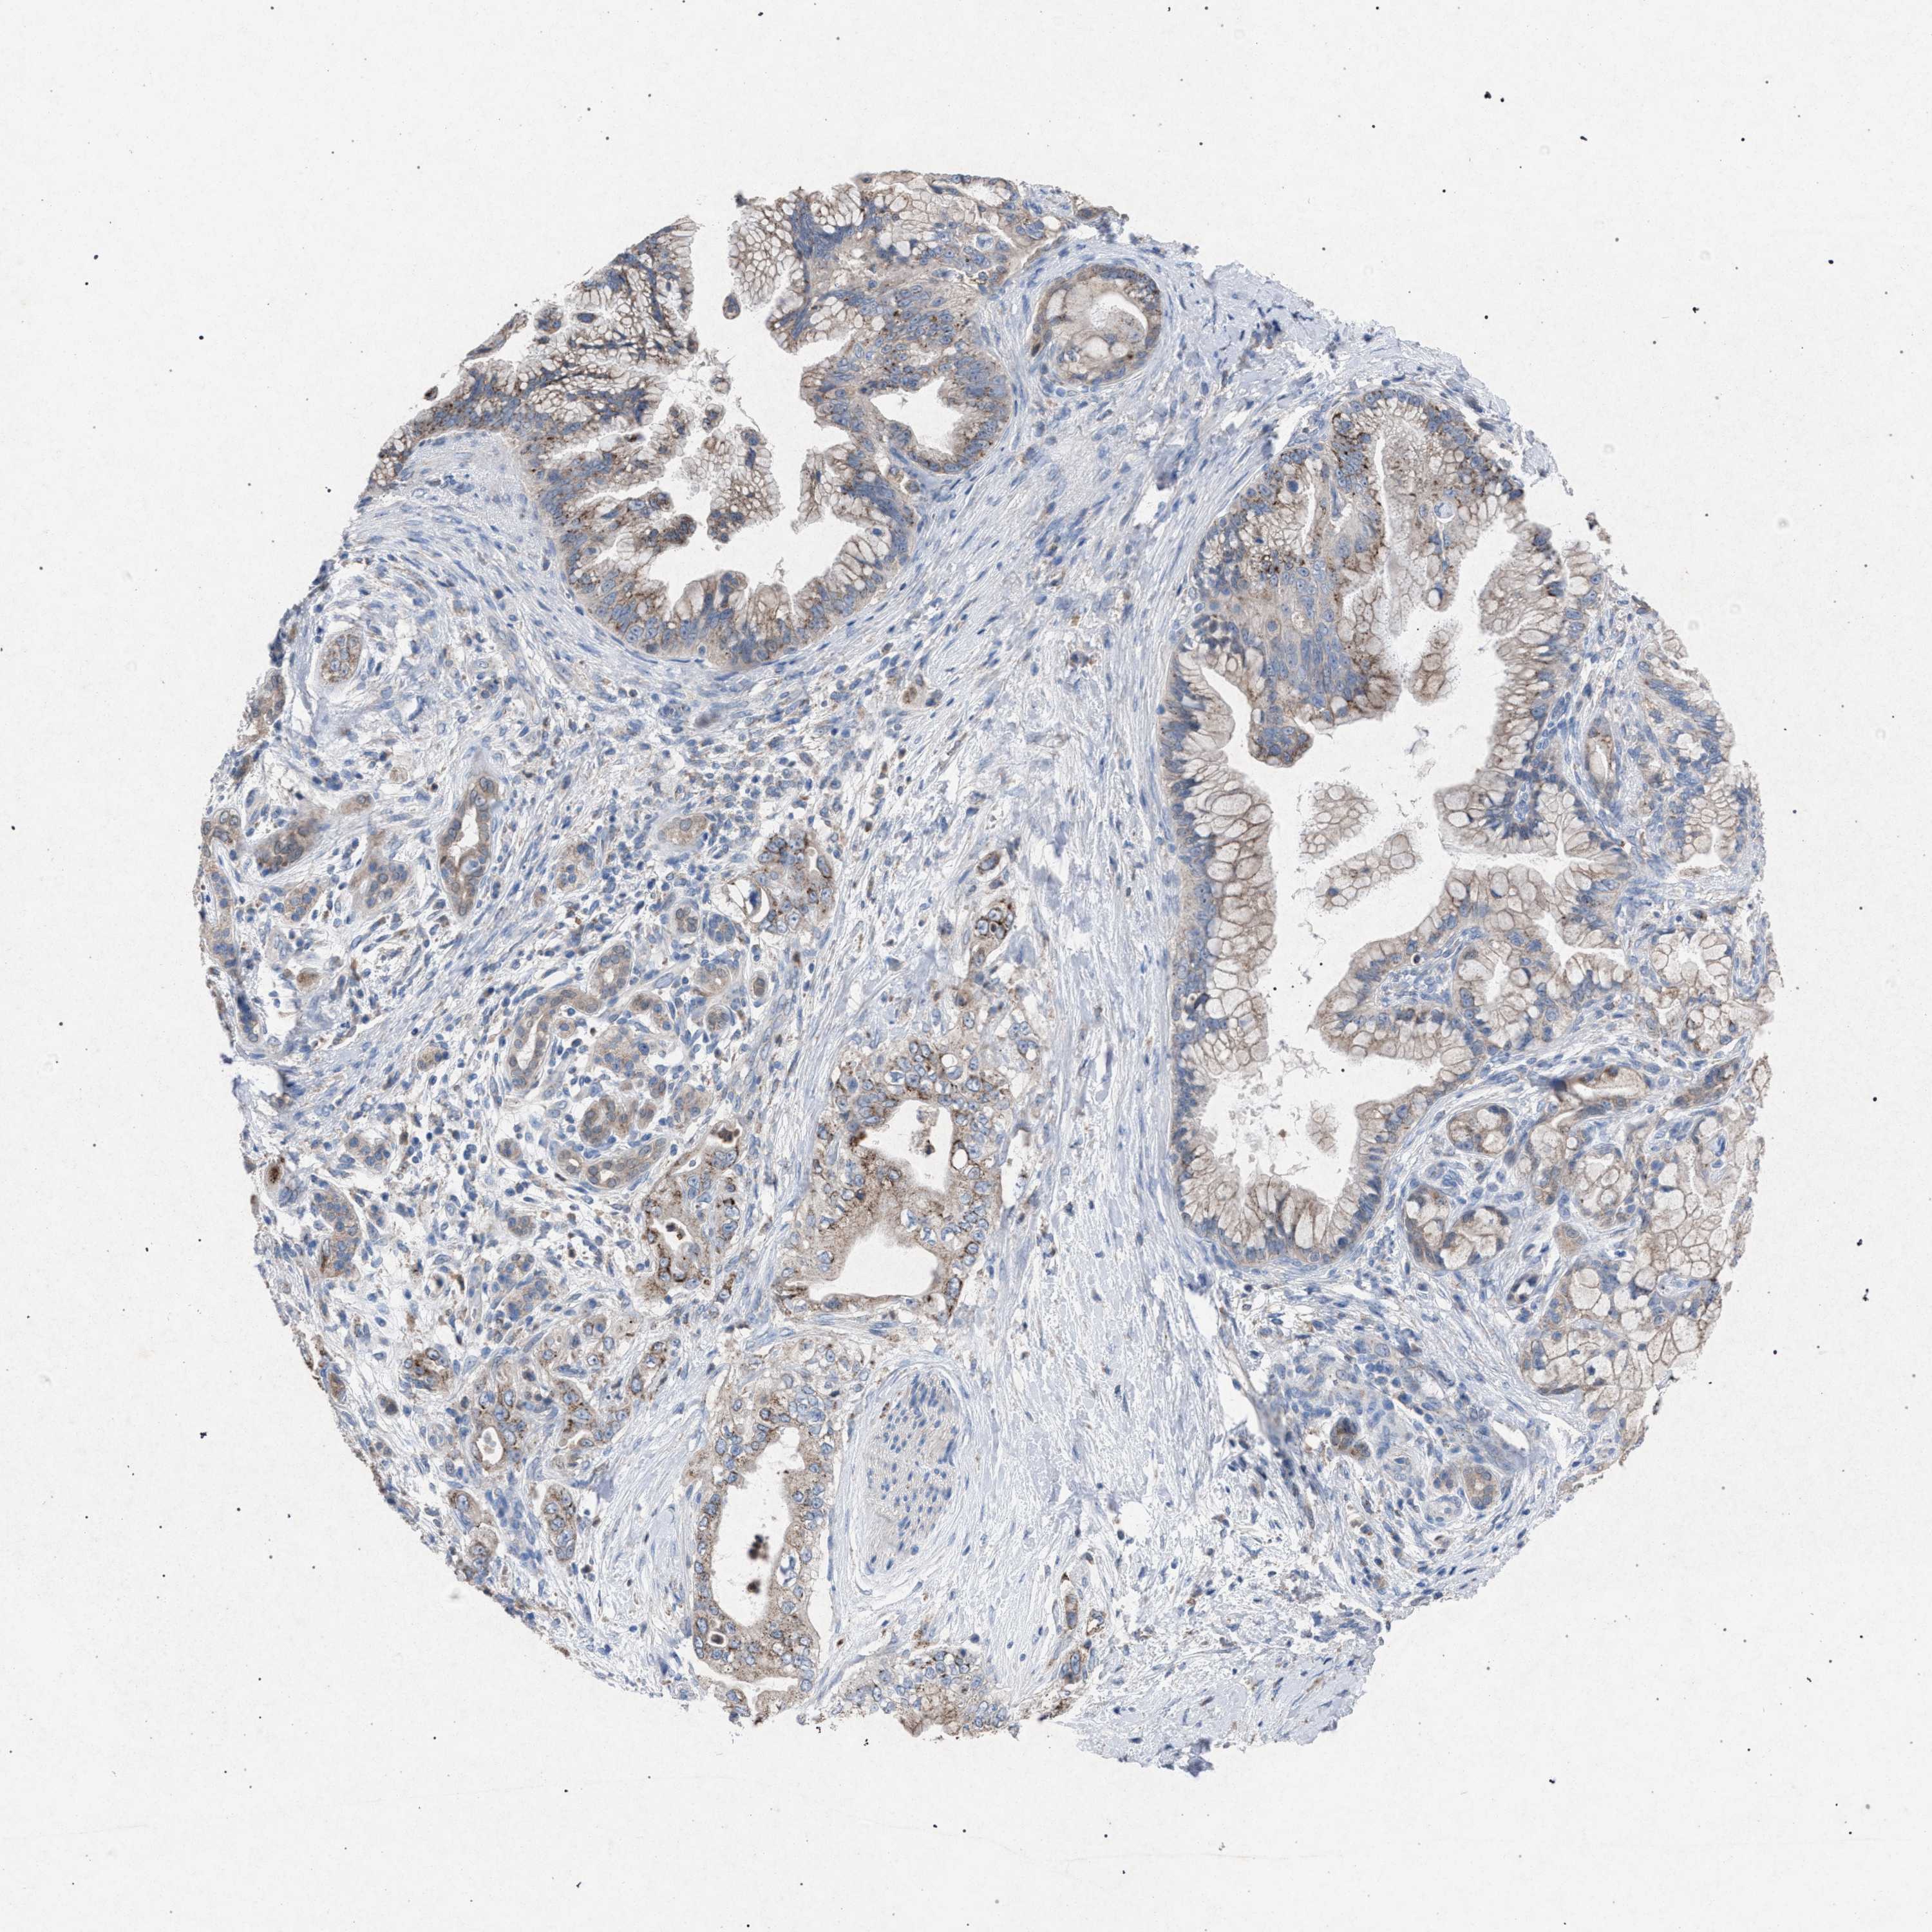

PANCREATIC CANCER - Protein expressioni

A mouse-over function shows sample information and annotation data. Click on an image to view it in a full screen mode. Samples can be filtered based on level of antibody staining by selecting one or several of the following categories: high, medium, low and not detected. The assay and annotation is described here.

Note that samples used for immunohistochemistry by the Human Protein Atlas do not correspond to samples in the TCGA dataset.

Antibody stainingi

Antibody staining in the annotated cell types in the current human tissue is reported as not detected, low, medium, or high, based on conventional immunohistochemistry profiling in selected tissues. This score is based on the combination of the staining intensity and fraction of stained cells.

Each image is clickable and will lead to virtual microscopy that enables deeper exploration of all samples and also displays staining intensity scores, fraction scores and subcellular localization as well as patient and tissue information for each sample.

Antibody HPA021302

Antibody HPA021311

Antibody HPA021479

Adenocarcinoma, NOS